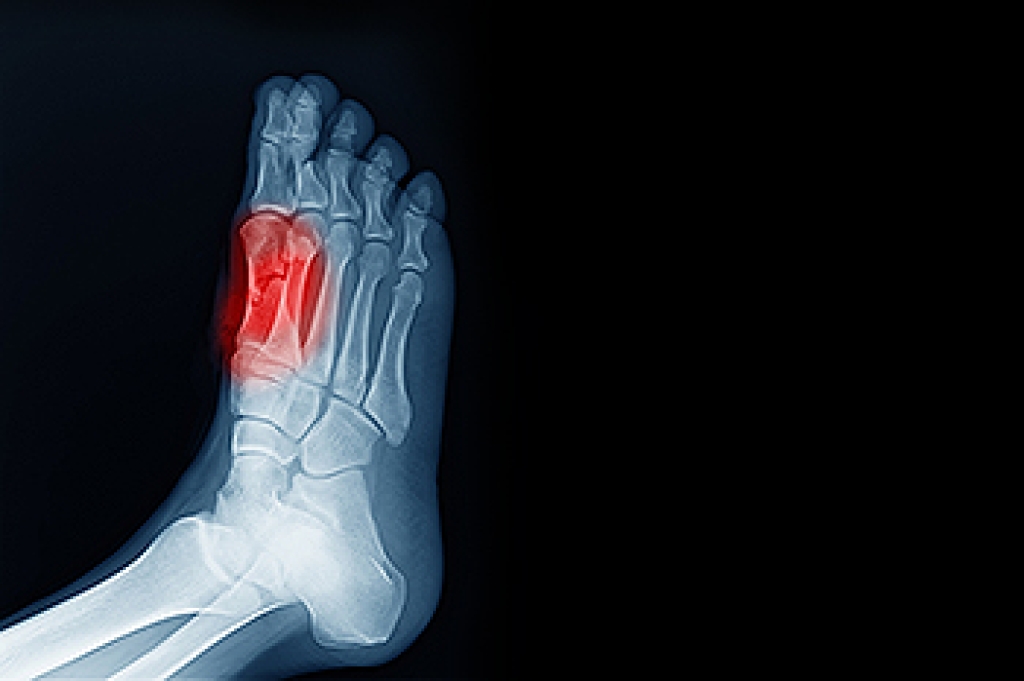

When the sesamoid bones in the ball of the feet become inflamed, an individual may develop a foot condition that is known as sesamoiditis. Patients who have this ailment often want to learn about potential remedies, as it can sometimes be painful. The answer is that there are many different steps that a patient may take while consulting with their podiatrist to address sesamoiditis. One potential technique that may be helpful to consider is known as immobilization. A patient may try immobilizing the affected foot by placing it in a cast or by using crutches. By doing so, a patient can effectively ensure the affected foot has time to rest and recover. As a result, there will be less force on the foot, and the sesamoid bones may get the opportunity to heal. If you are currently living with sesamoiditis, it is strongly suggested that you schedule an appointment with a podiatrist today.

Sesamoiditis is a condition of the foot that affects the ball of the foot. It is more common in younger people than it is in older people. It can also occur with people who have begun a new exercise program, since their bodies are adjusting to the new physical regimen. Pain may also be caused by the inflammation of tendons surrounding the bones. It is important to seek treatment in its early stages because if you ignore the pain, this condition can lead to more serious problems such as severe irritation and bone fractures.